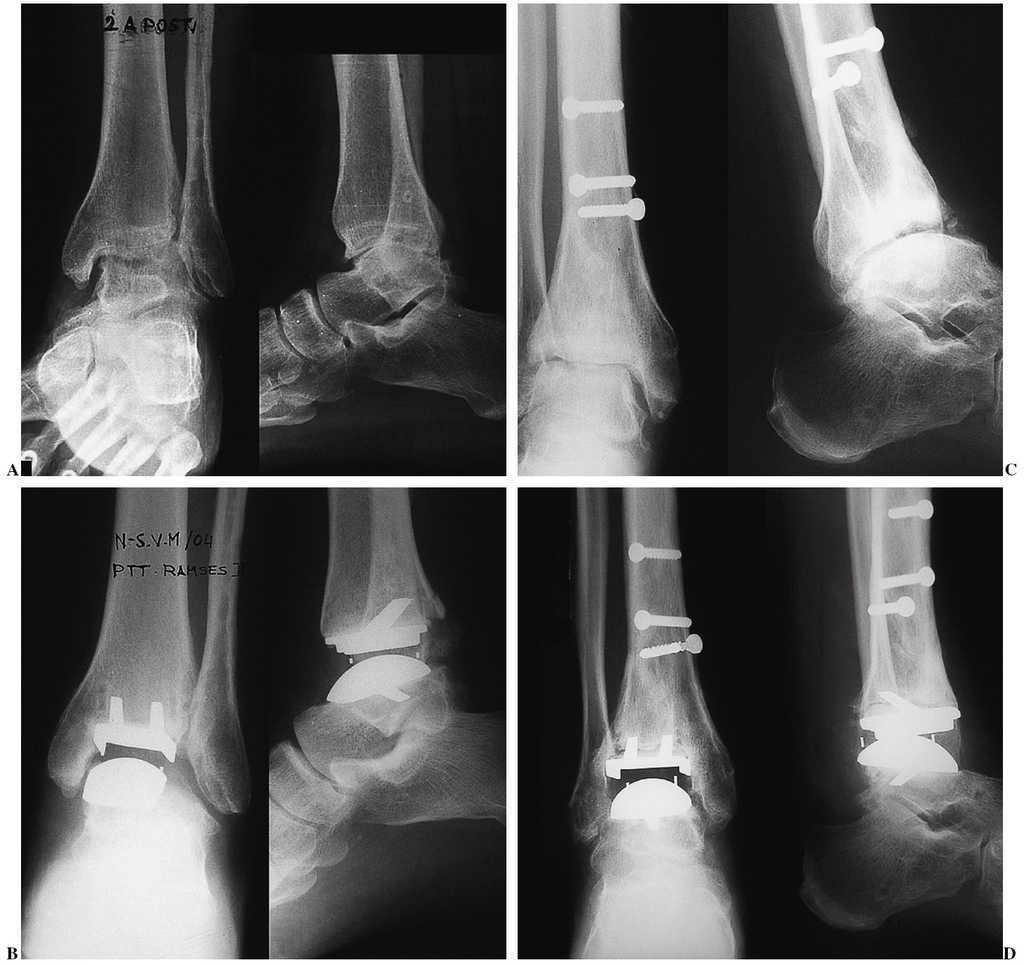

Figura 7. Paciente con artritis reumatoide. Lesión bilateral. Imágenes anteroposterior y lateral. Control radiográfico de los implantes, anteroposterior y lateral. Tobillo derecho (A) y (B). Tobillo izquierdo (C) y (D):